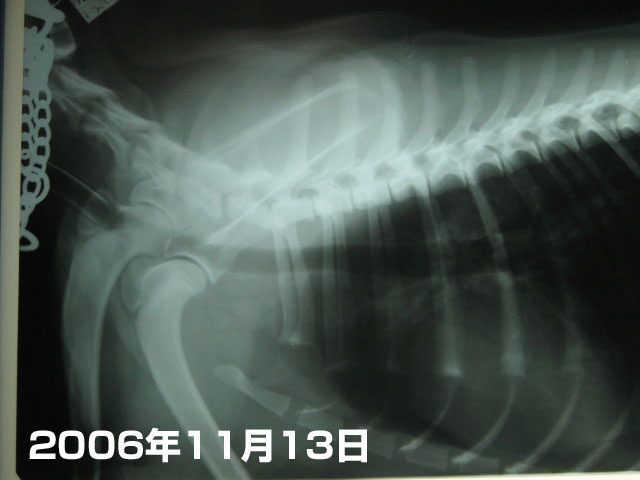

まずは気管。

これは2006年11月13日。不妊手術の歳に撮ったレントゲン。

気管ののど元にはまだ麻酔チューブが入っている状態なので、のど元の気管の太さが確認できなかった。

で、これが本日。

頚椎の下に沿って黒く写っているホースみたいなのがもいたんの気管。

太さや形に問題なし(^-^)v

次に肺。

1枚目の2006年11月13日、不妊手術の歳に撮ったレントゲンと比べてみるとわかるけど、

肺(肋骨にくるまれた中央の下の方の白っぽい部分)が、少々【石灰化】して?白っぽくなっている。

たぶんそれはホルモン(上皮小体?)が不安定な状態らしく、カルシウム分は控えたほうがよいでしょうって。